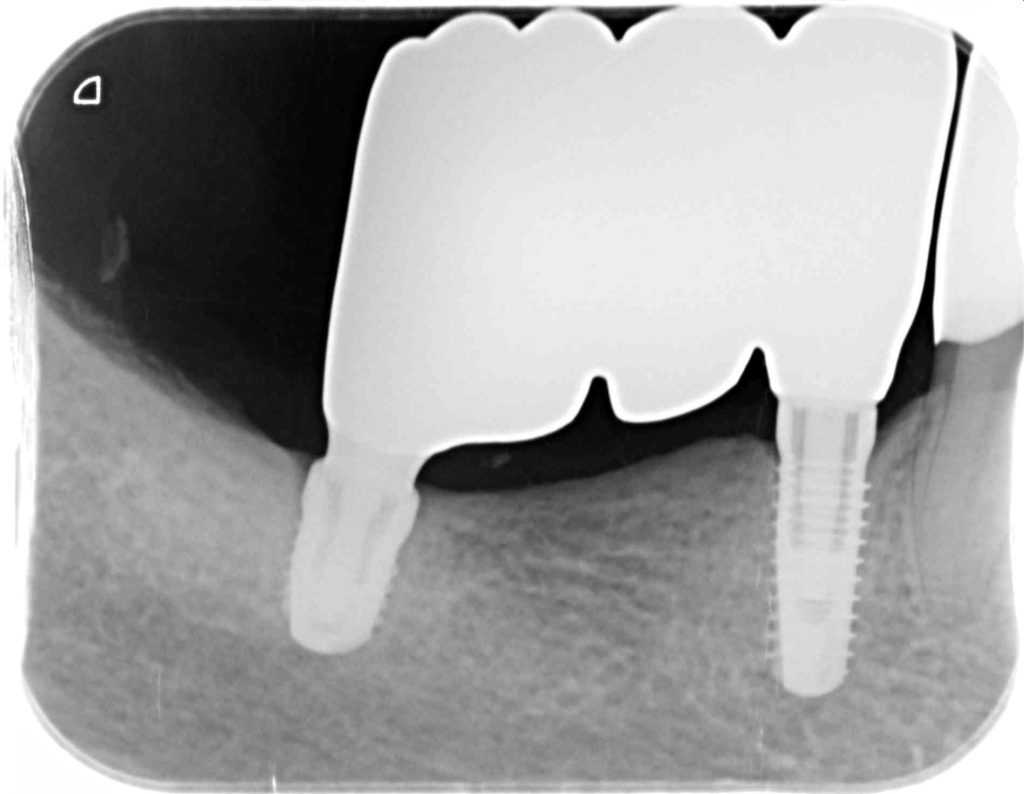

その場合、ショートインプラント(8mm以下)と言って通常より長さの短いインプラントを埋入する事があります。

様々な条件から侵襲の大きな骨造成や歯肉移植などせずに治療期間を短く、ご負担の大きな外科処置を避ける選択肢をご提案いたします。

高齢の為、早期の咀嚼機能の回復を目指しショートインプラントを用いた咬合機能の回復を目指しました。

下記の症例にかかる費用 約150万円(税抜)